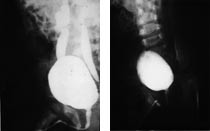

I femårsperioden 1990 – 95 ble alle barn som trengte kirurgisk behandling for vesikoureteral refluks forsøkt behandlet via cystoskop. Behandlingen foregår hovedsakelig som dagkirurgi. I narkose injiseres 0,2 – 1 ml teflonpasta under ureterostiet svarende til «kl 6». Ostiet blir da spalteformet på toppen av en submukøs «pute» (fig 1). Indikasjonen for denne behandlingen var den samme som vi tidligere hadde for reimplantasjon, dvs. refluks minst grad III (ev. grad II hvis motsatt side allikevel skal behandles), tegn til nyreaffeksjon, flere episoder av urinveisinfeksjon til tross for medikamentell profylakse, ingen mulighet for å gjennomføre profylakse av medisinske og/eller sosiale årsaker og ingen tilbakegang av refluks etter flere års medisinsk behandling. Vi benytter internasjonal gradering I – V (fig 2) (8). 102 barn med refluks til 155 uretre ble behandlet av samme barnekirurg (KOV). Det var 78 jenter og 24 gutter, i alderen ti uker til 14 år. Både primær refluks, sekundær refluks (nevrogen blære, infravesikal obstruksjon) og kompleks refluks (refluks ved dupleksuretre, ureterektopi, ureterocele, og etter operasjon) er tatt med (tab 1). Rutinekontroll med miksjonscystografi og ultralydundersøkelse av urinveier ble avtalt henholdsvis tre og 12 måneder etter behandling.

Gjentatt behandling ble utført i 22 refluksuretre, med opphør av refluks i 13, bedring av refluks i seks og uforandret i tre. Hos 13 pasienter, 18 refluksuretre, ble det nødvendig med reimplantasjon. De fleste av disse hadde kompleks refluks. De røntgenologiske funn før og etter behandlingen illustreres i figur 3 der miksjonscystografi tre måneder etter behandlingen viser at refluksen er forsvunnet på begge sider. Ved ultralydundersøkelse av blæren kan teflonpasta sees som ekkorike, skyggegivende små oppfyllinger ved ostiene (fig 4).